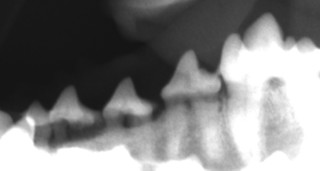

歯周病は歯周組織、歯槽骨が破壊されていく病気です。つまり、外からは見えない歯肉の中で起きている病気なのです。歯肉の中の歯周組織がどうなっているかを調べるには、レントゲン検査や麻酔下でのプロービング(器具を使って歯周ポケットの深さを測る)が必要となります。もちろん見た目だけでも大体の状態は分るのですが、歯の表面はキレイでも歯肉の中で歯周病が進行していて歯が抜けていってしまうワンちゃんも時々います。

見ためはキレイですが

レントゲンでは歯槽骨が破壊されています